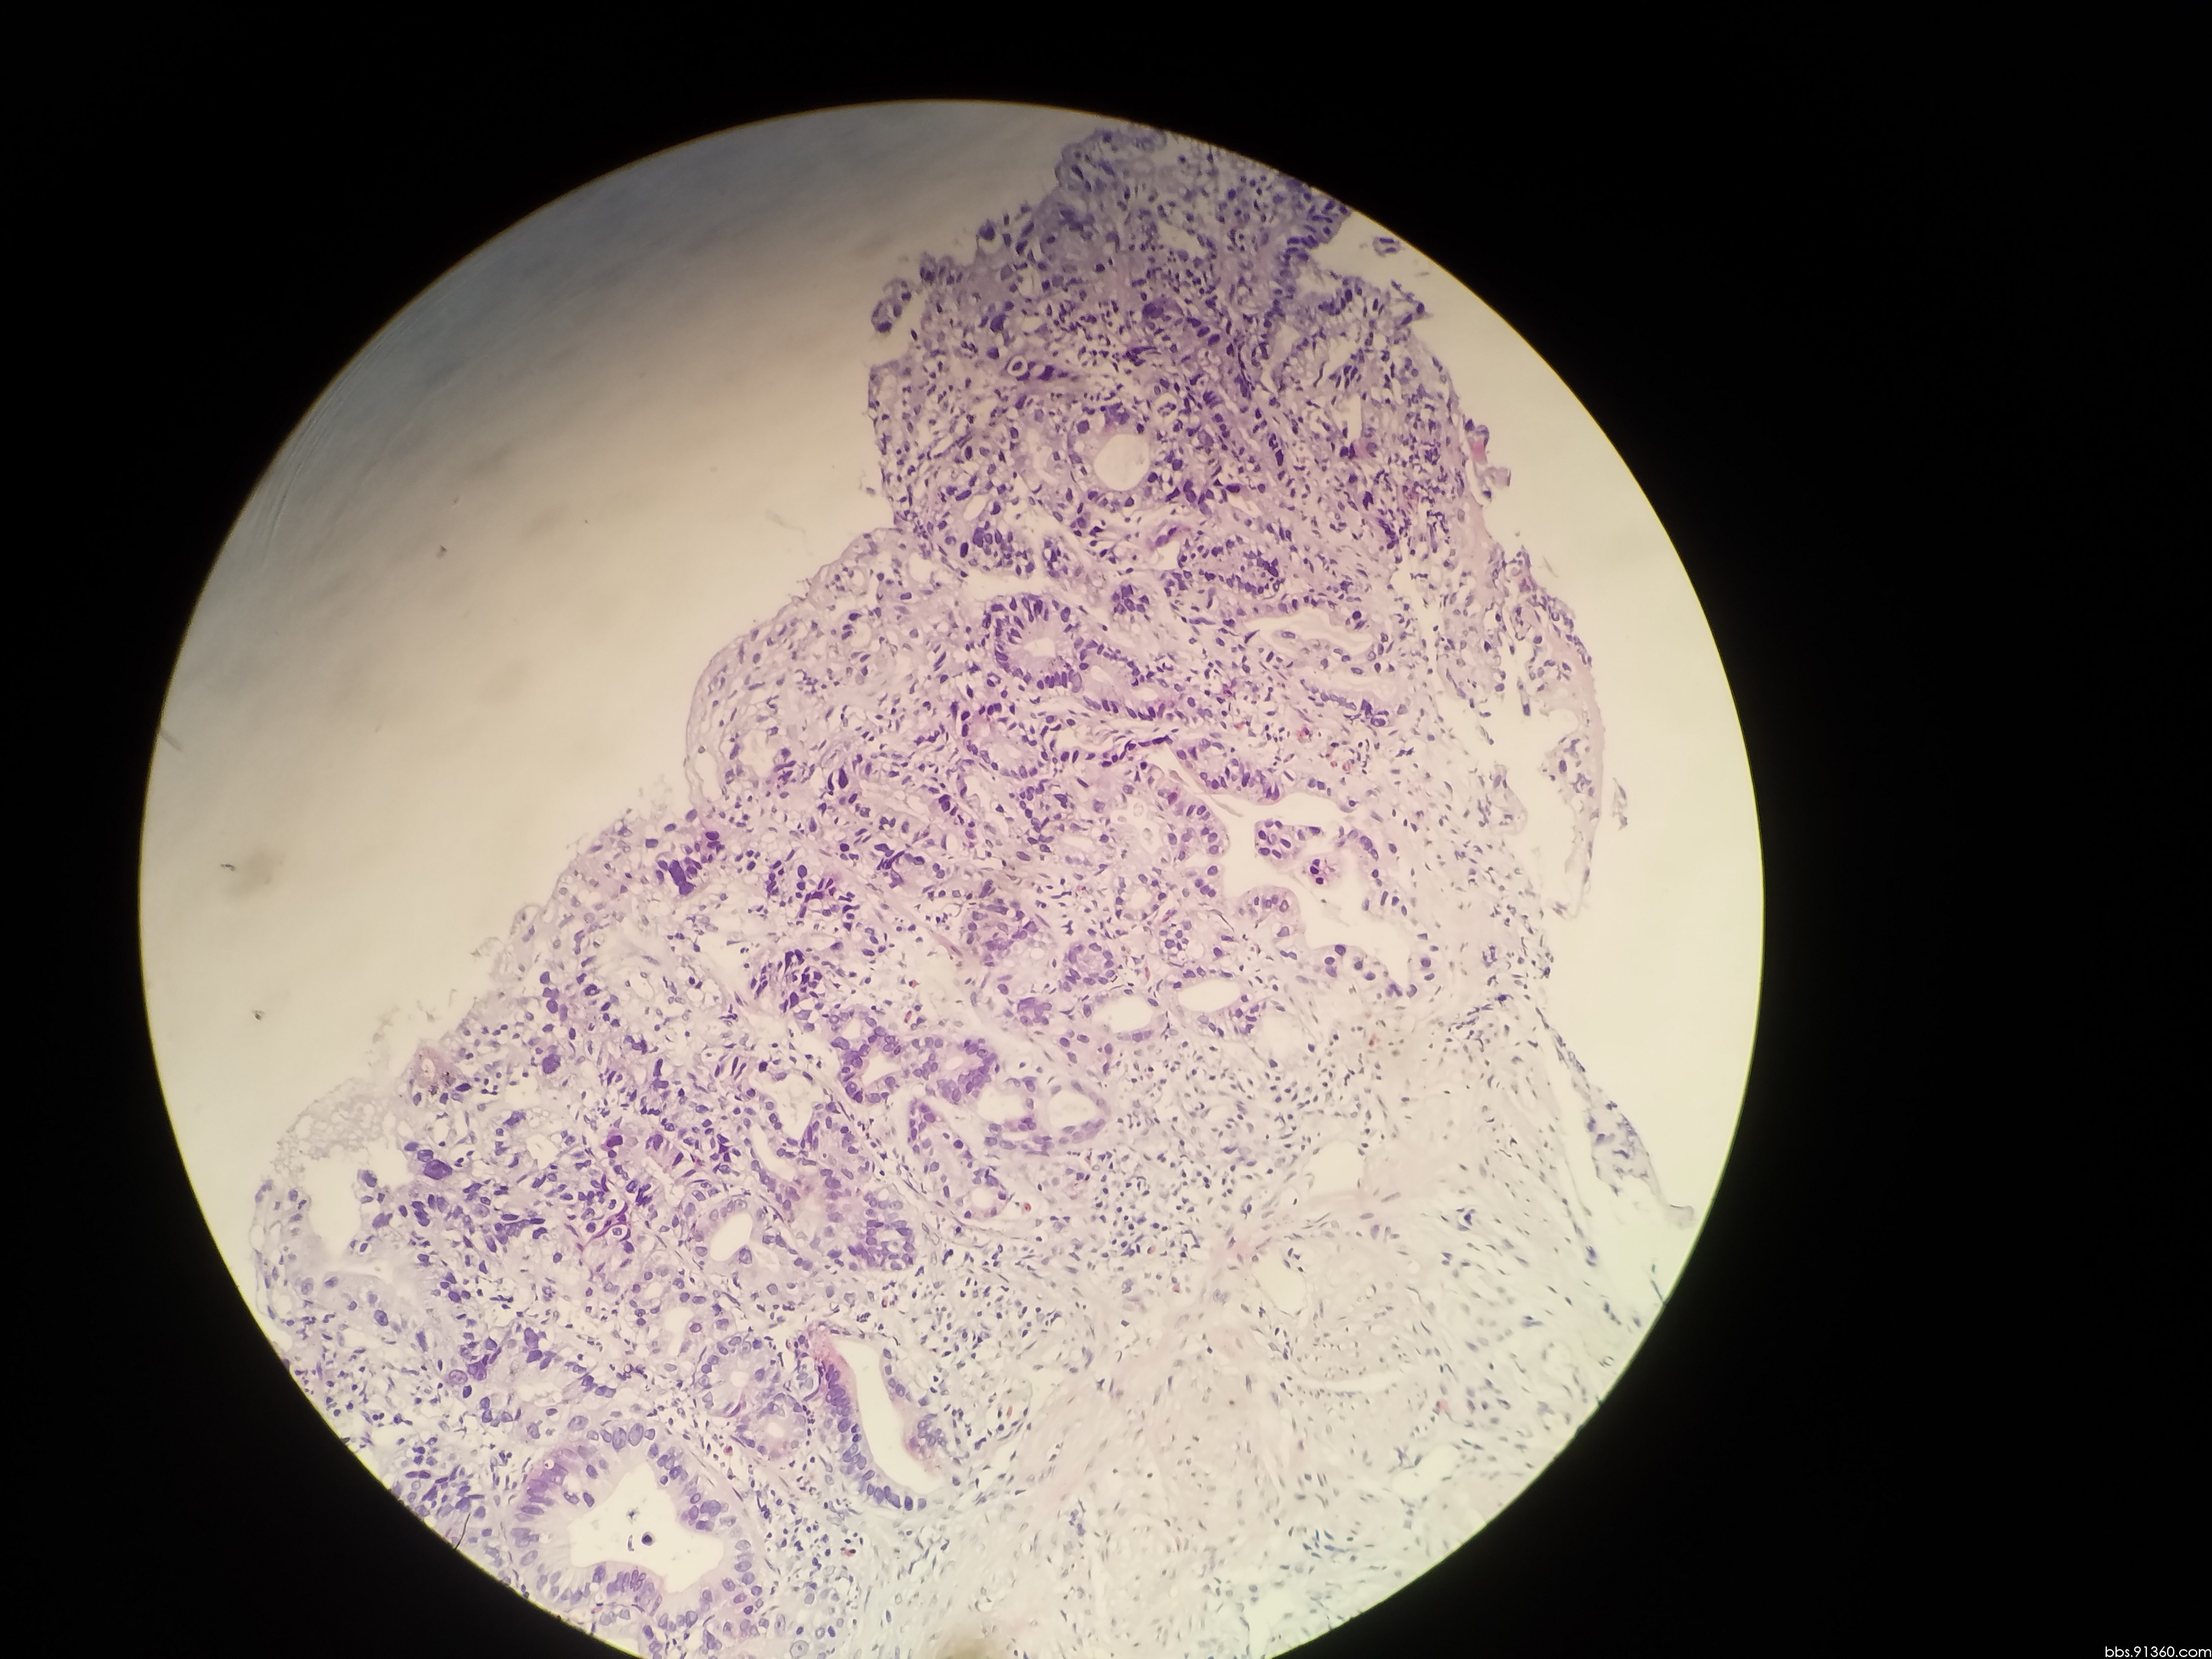

胃窦部黏膜组织活检镜下如图所示胃黏膜发生的有关病变的描述

胃窦部黏膜组织活检镜下如图所示胃黏膜发生的有关病变的描述错误的是

胃窦部黏膜活检

胃窦部黏膜活检

胃窦部黏膜活检

胃窦部黏膜活检